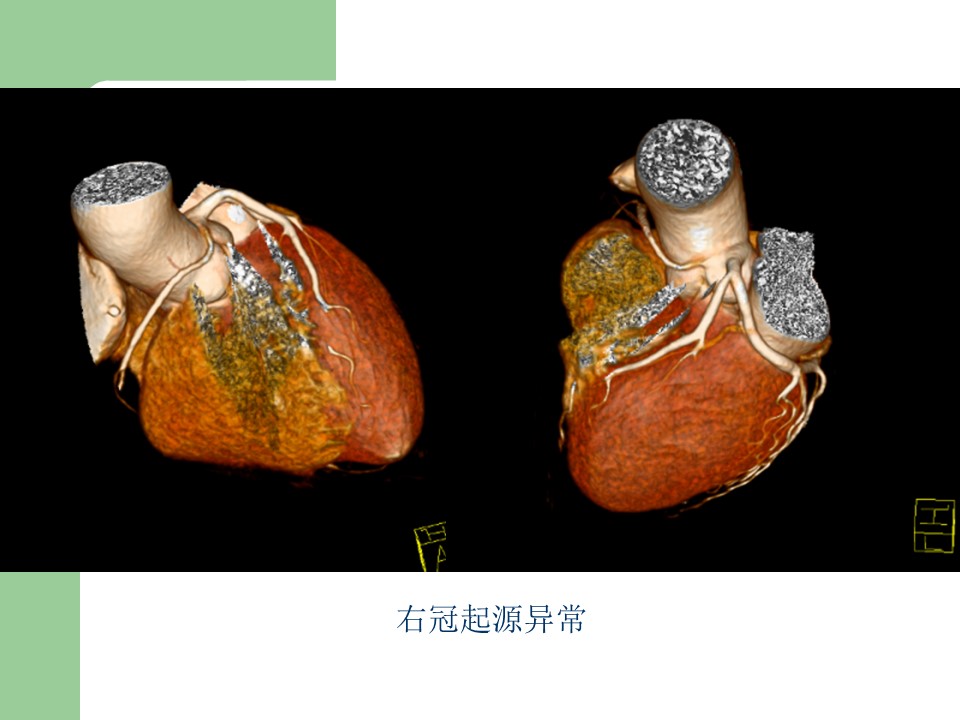

“冠状动脉常见疾病的双源CT表现” 的相关文章